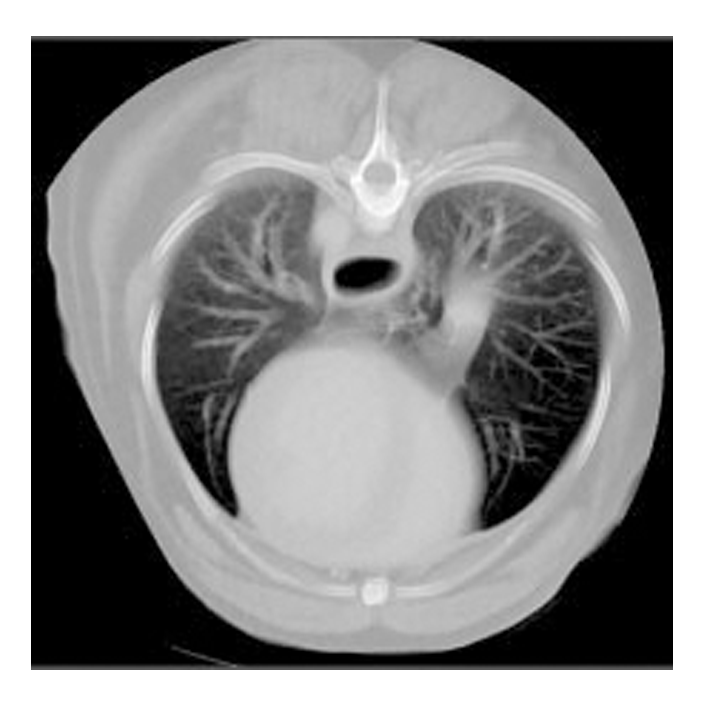

Das NewTom 5G XL VET Compact ist die ideale Lösung für Praxen mit geringem Platzangebot.

Dieses CBCT vereint die Vorzüge des NewTom 5G XL mit einem speziell entwickelten Carbon CBCT Tisch.